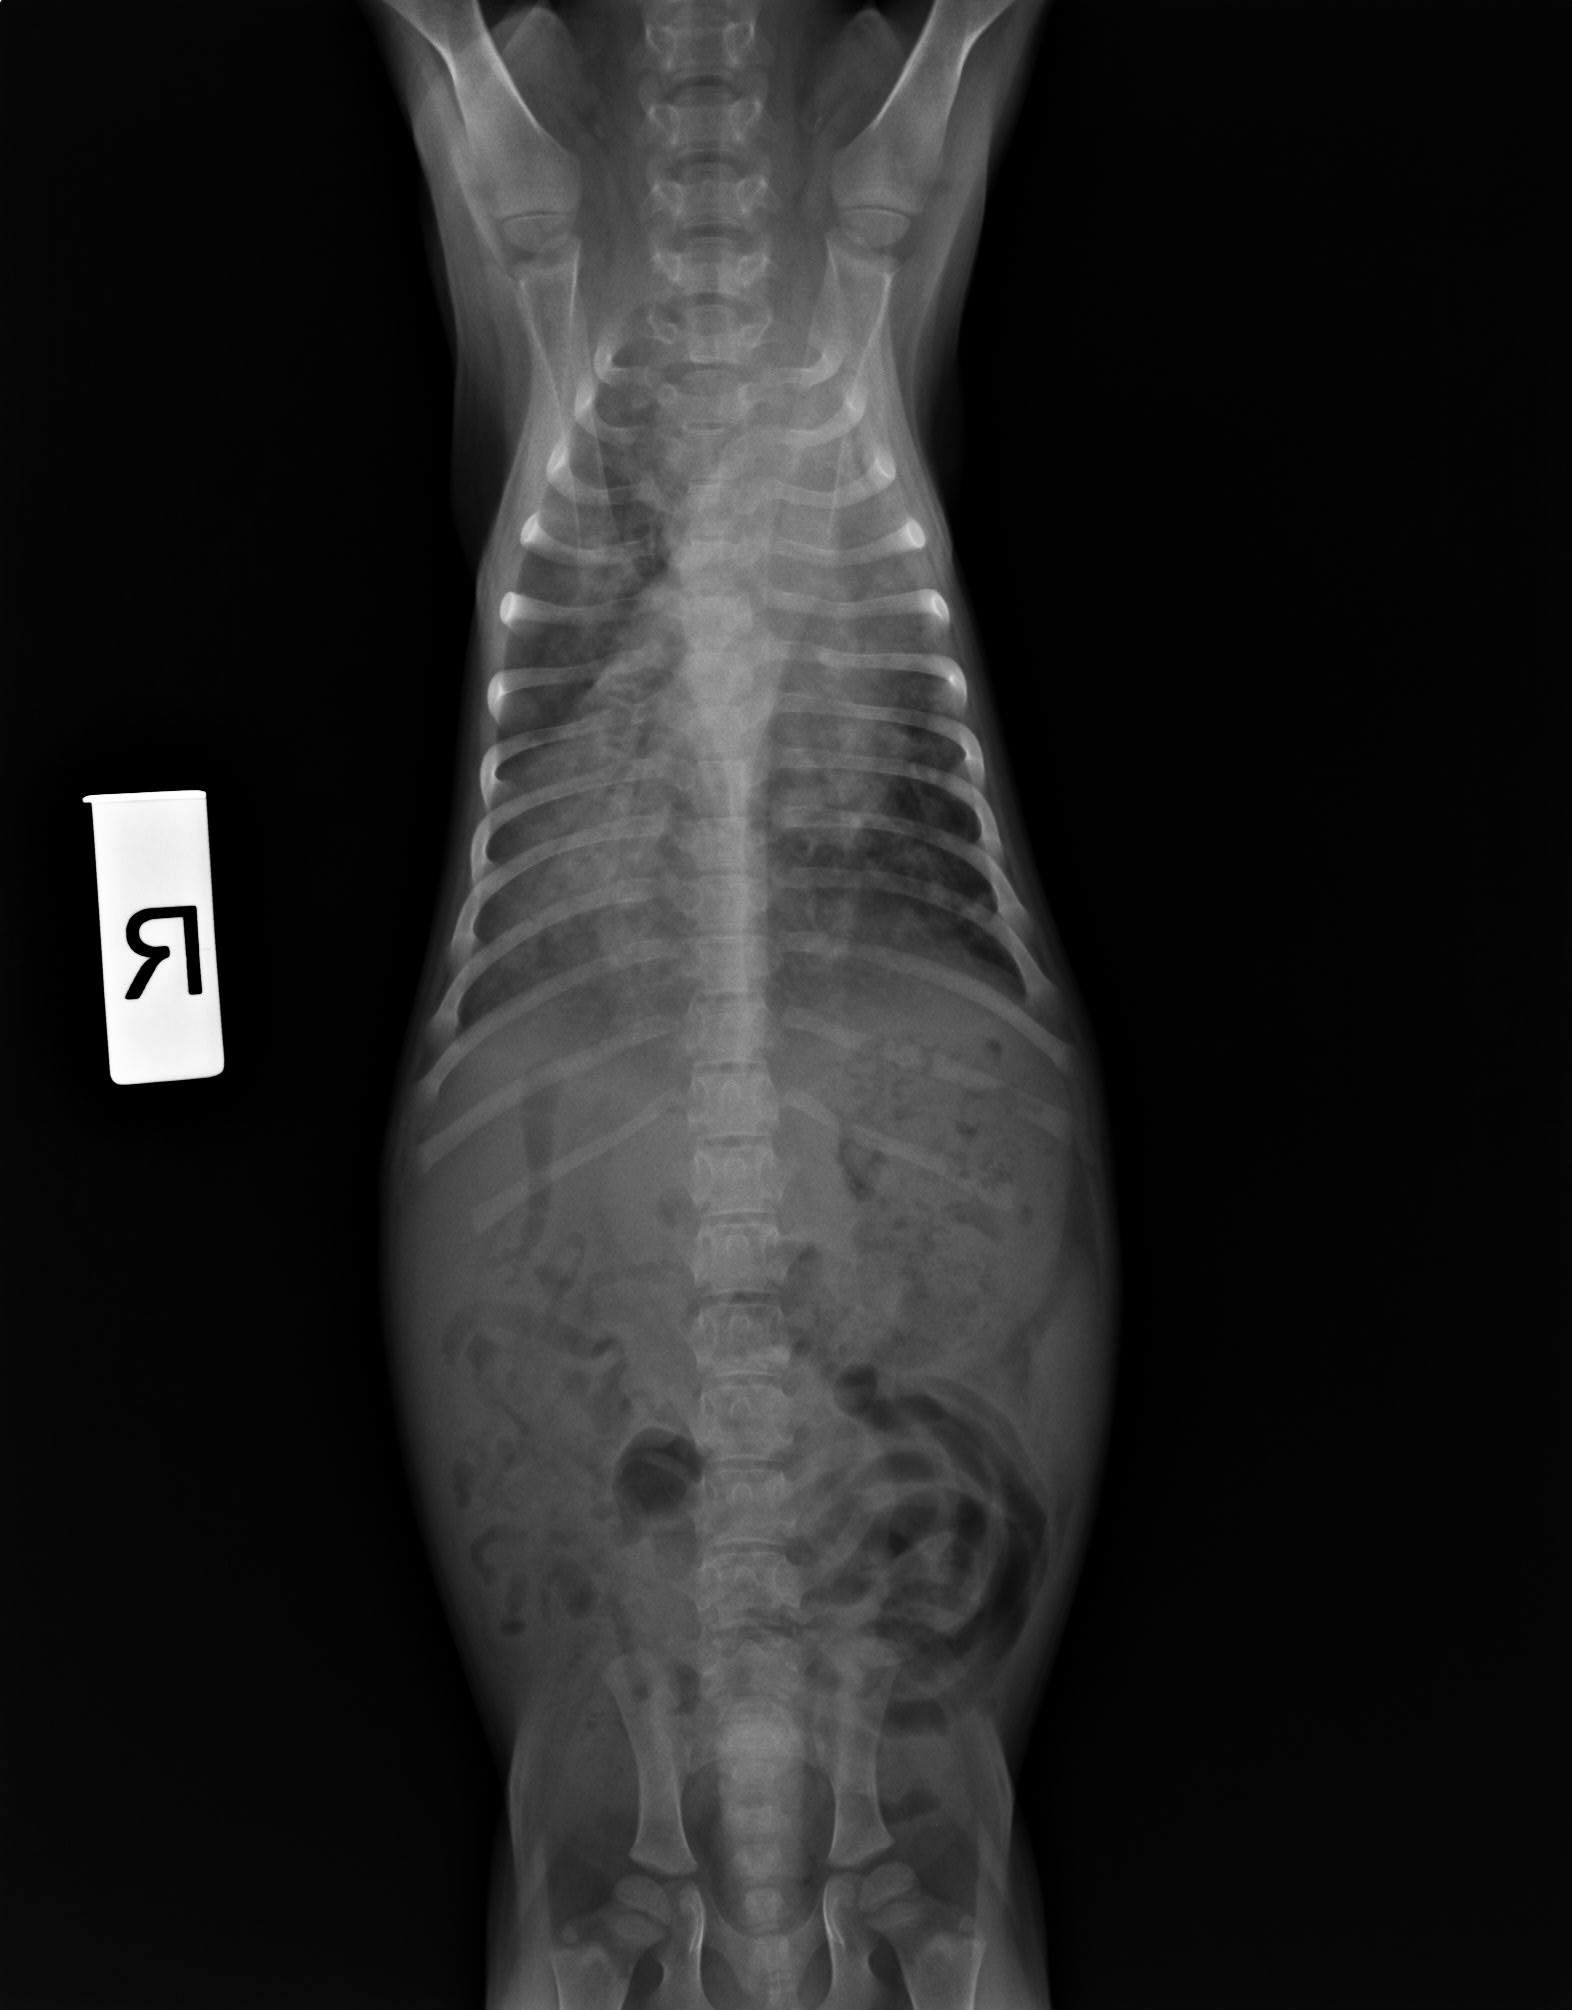

1L RT 下面穿X光片

我家这货两个半月左右 咳了大概半个月 今天体温突然升高39.9 就带去宠物医院

医生说很严重,不知道真的假的